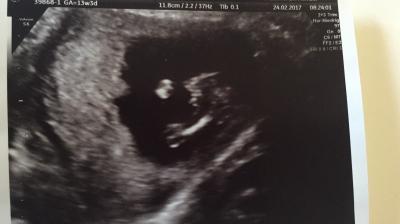

Heute hatte ich wieder Termin beim FA. Alles ist super, Krümel ist ca 9cm groß und 80g schwer. Ein Outing gab es auch :) Gehören nun auch zur Fraktion. Das Outing ist zwar "nur" 99% aber meine Ärztin hat von mehreren Winkeln geschallt und es hat sich nichts geändert xD Leider lag Krümel für ein schönes Foto recht doof und das einzige was er beim Bewegen gut fand war die Beinchen weit auseinander zu machen. Ansonsten ist alles in der Norm. Nächster Termin ist dann am 24.3 Liebe Grüße

Bild zu FA Termin - Forum für August - Mamis

Glückwunsch:) das sieht arg nach junge aus :) ähnlich wie mein Bild am Dienstag:)